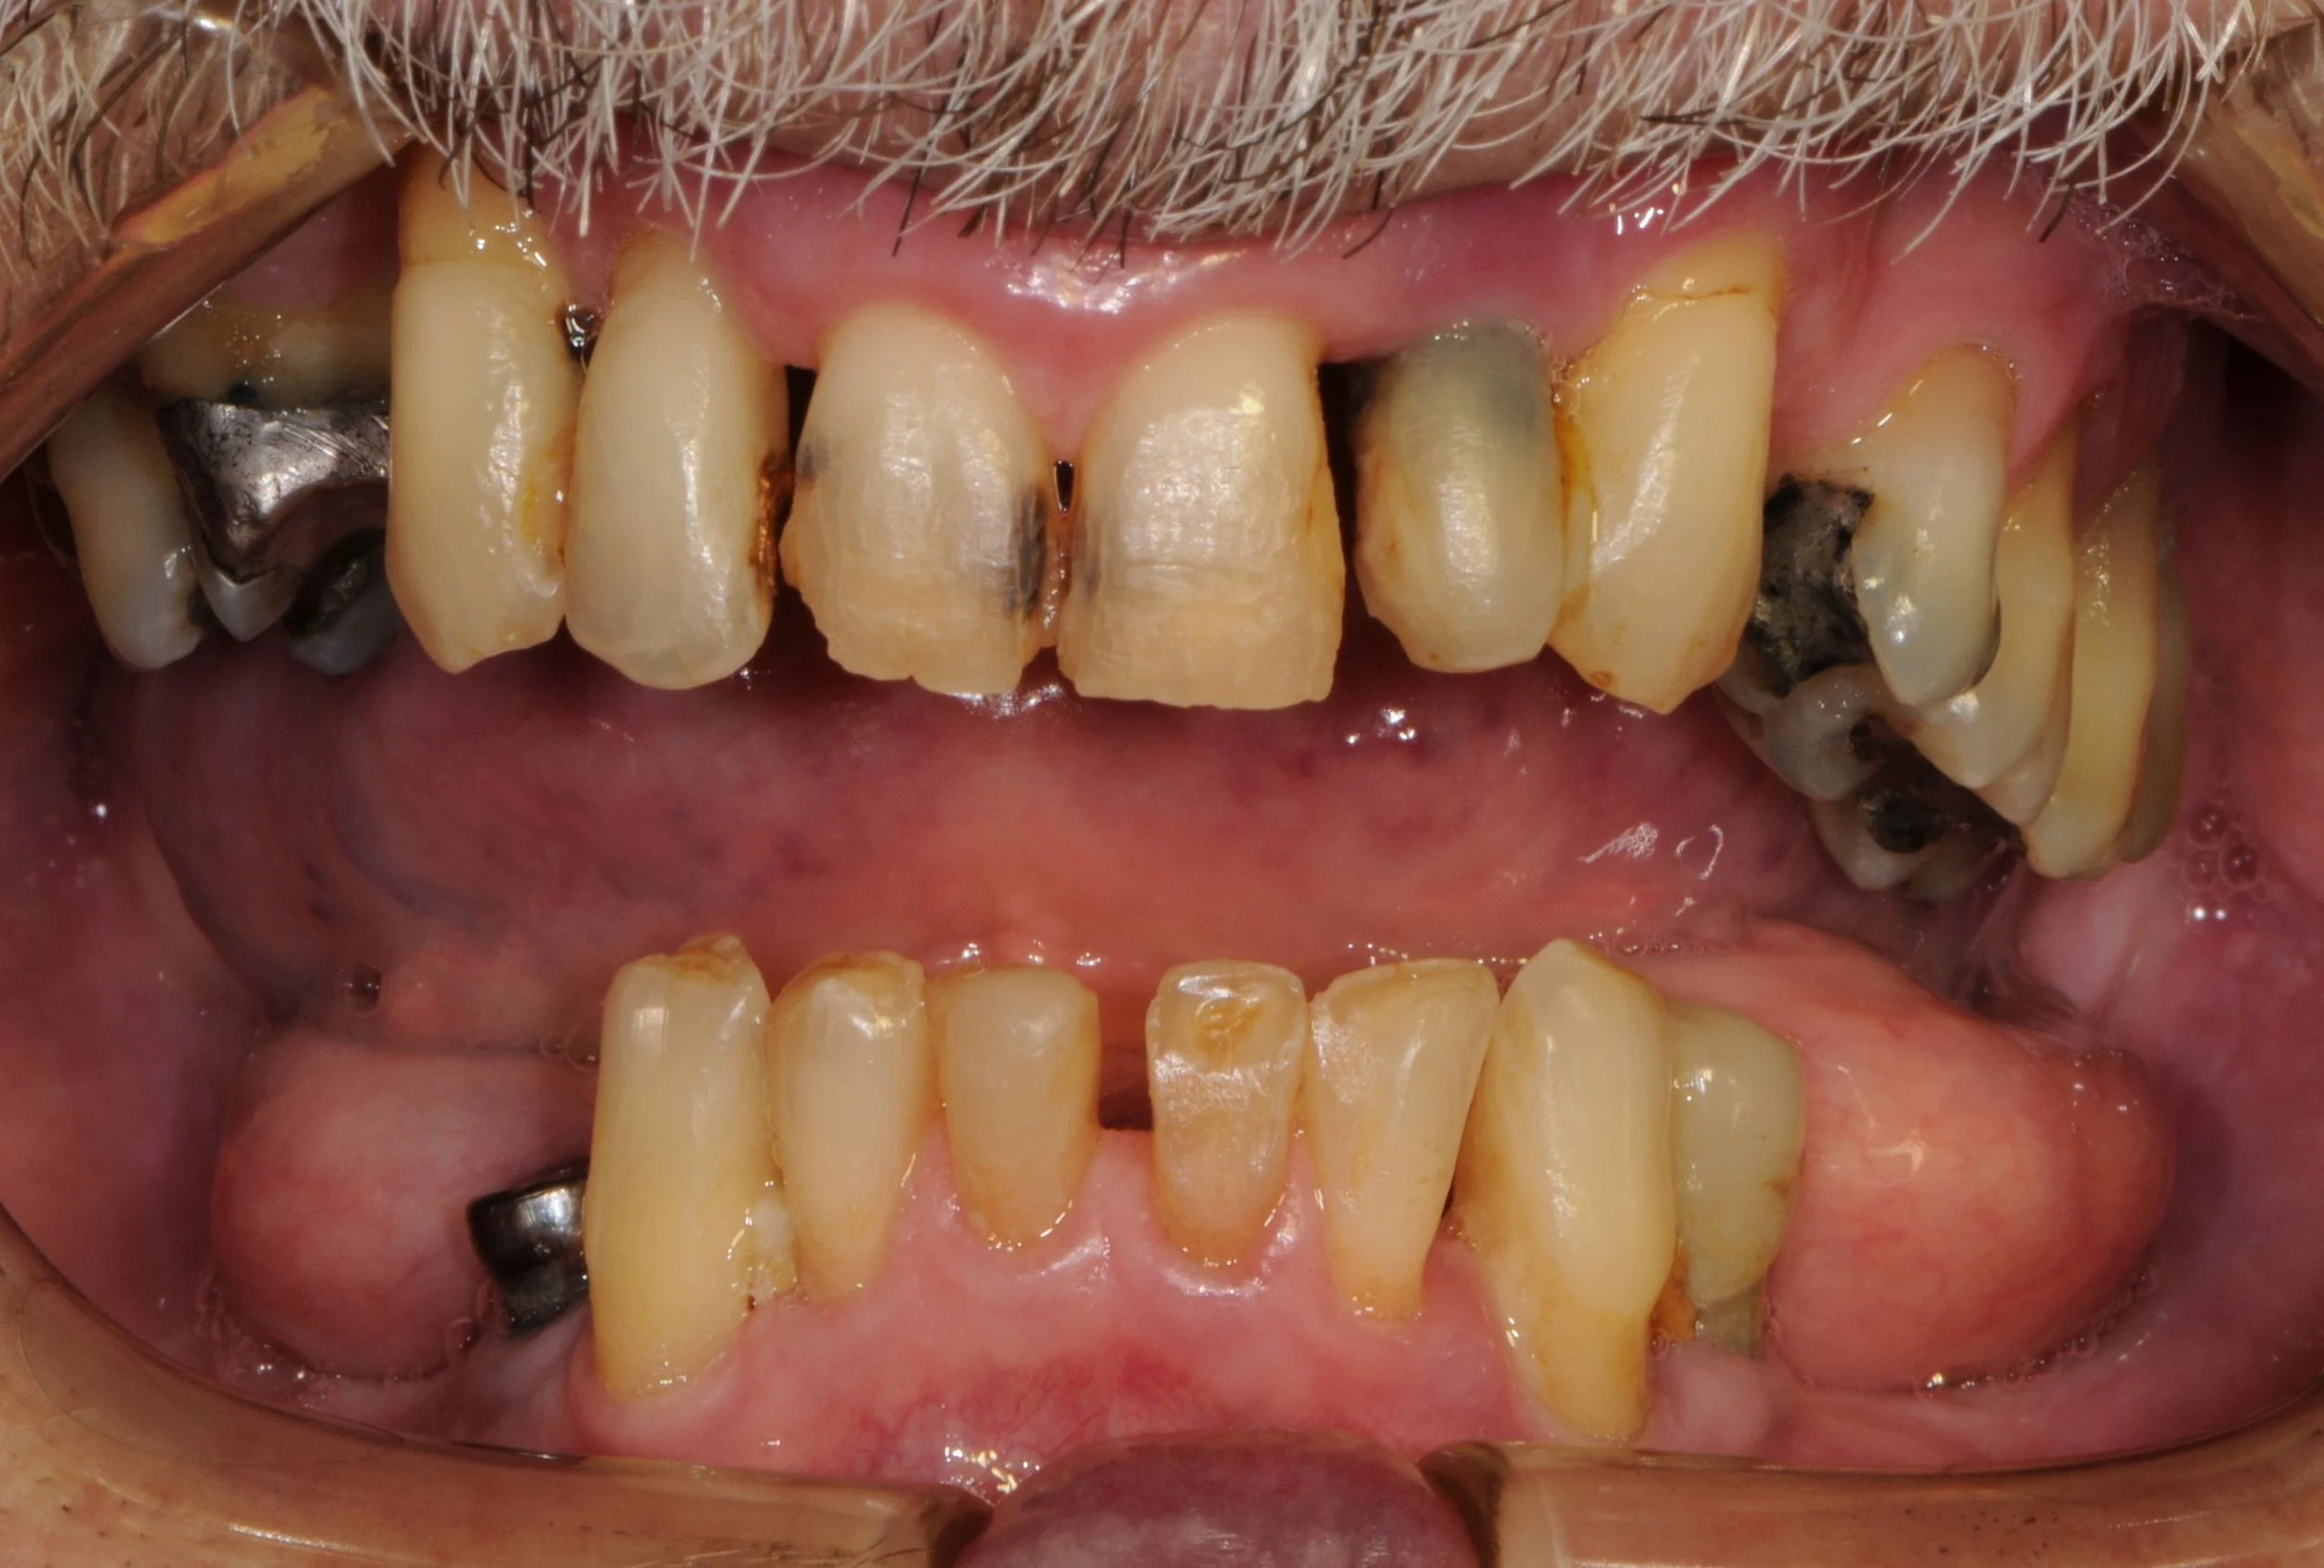

This 50 year old patient unfortunately developed cancer in his mouth on the lower left hand side which required complete resection or removal of the teeth, gums and lower left jawbone by a Facio-Maxillary Surgeon.

-

The lower jawbone was reconstructed by harvesting bone from the tibia of the leg along with a soft tissue graft consisting of calf muscle and surrounding fat tissue. Two pieces of bone were splinted in place with metal plates and screws to the remaining jawbone .

The patient was referred to me at Lismore in 2021 to replace the missing teeth with a fixed prosthesis involving an implant bridge. I designed the bridge on an OPG radiograph and issued instructions to my ceramist technician to fabricate a diagnostic wax up of the future teeth .